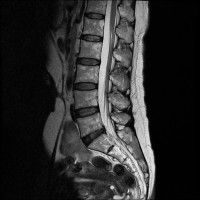

경추 요추 디스크 둘다 있는 상태고 경추몇번에서 몇번사이 요추몇번에서 몇번사이인지 알려주세요

허리

• 4번 째 사진